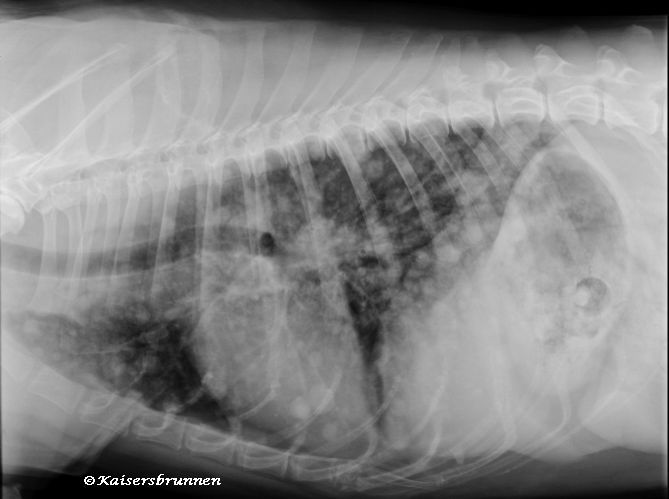

Röntgen (Thorax)

Source: tierarzt-nidderau.de

Die klinischen anzeichen von leberkrebs im stadium 4 bei hunden sind die folgenden: Eine konkrete antwort kann nicht gegeben werden. Urin hat eine orange farbe.